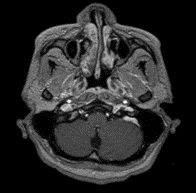

Una semana más reingresó a por servicio de urgencias debido a una exacerbación aguda del dolor abdominal previo y emesis. Se realizaron nuevos estudios de imagen complementarios: la colangiopancreatografía por resonancia magnética fue negativa, descartando enfermedades de la vesícula biliar y una nueva resonancia magnética contrastada del cerebro y la columna cérvico- descartó mielopatía en la columna vertebral, pero mostró un aumento considerable en la extensión del área de la lesión postrema con un notorio realce con gadolinio (Imagen 2). Se indicó un pulso de metilprednisolona de 1 gramo durante 3 días, se realizó una reinducción de ciclofosfamida; recibió un total de 2 dosis durante su hospitalización. Fue dada de alta nuevamente con mejoría clínica con una orden de continuar con ciclofosfamida, medicación previa y una orden para un perfil complementario de síndrome de antifosfolípidos y anticuerpos anti-acuaporina 4. En un control ambulatorio posterior, el paciente no refirió nuevas recaídas y mostró una IgM anticardiolipina positiva e IgM positiva para la glicoproteína beta 2 I con anticuerpos anti-acuaporina 4 negativos. Se añadió una dosis baja de inhibidores de la agregación plaquetaria y se realizó un diagnóstico altamente probable de SAF secundario a LES.

Imágen 3 y 4. RM de columna cervical y torácica en plano sagital en secuencia T2 donde la ausencia de la lesión se demuestra.